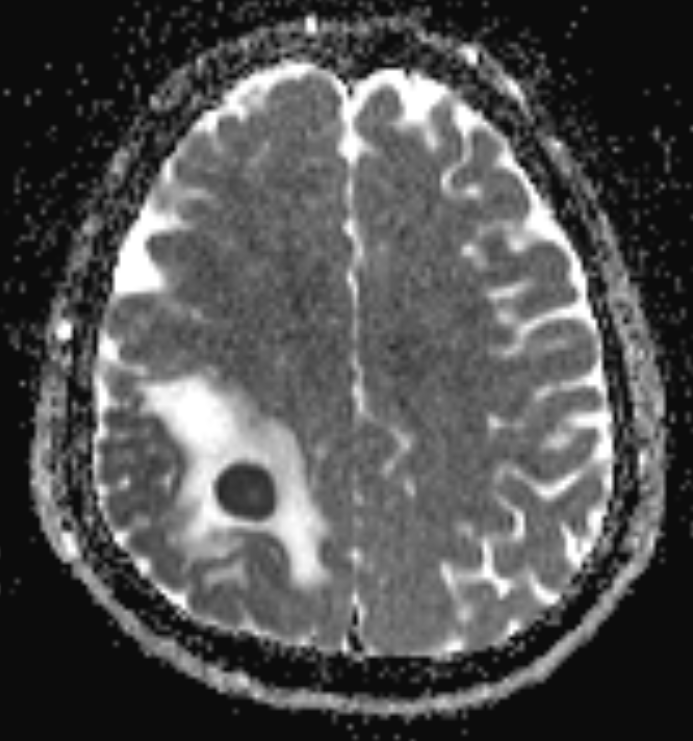

8.괴사된 조직, 백혈구, 세균이 혼합되면서 점도가 높은 농이 형성되고, 국소적인 고름 주머니가 만들어지며 병변의 용적이 증가함.

9.시간이 경과함에 따라 농양 주위로 섬유아세포와 교세포가 증식하여 피막이 형성됨.

피막은 감염 확산을 억제하는 방어기전이지만, 동시에 병변을 고형화함.

10.피막화된 농양은 종괴 효과를 유발하여 인접 뇌조직을 압박함.